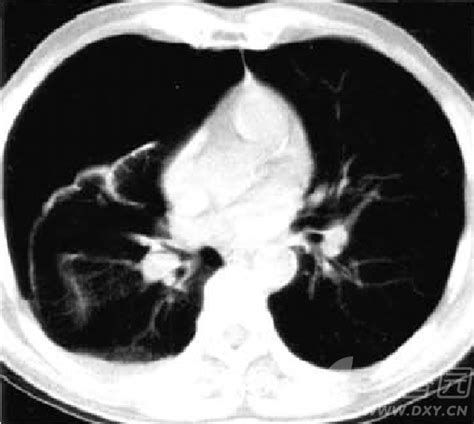

肺癌是是我国发病率最高的癌症之一。在我国,肺癌发现时多以中晚期为主,除发现时间晚,肺癌的另一个特点是发病年龄年轻化。 2014年《国际癌症杂志》统计报告中,中国肺癌患者的平均发病年龄在40~50岁。肺癌患者五年生存率仅16%。 而早期肺癌患者Ia期肺癌5年存活率则可达80% ~ 90%,Ib期肺癌5年存活率也可达70%,足以说明“肺癌三部曲——早发现、早诊断、早治疗”的重要性! 低剂量薄层CT是一种精准的肺癌早期筛查方式。它的辐射剂量约为传统胸部CT检查剂量的1/6~1/10。在美国大样本统计中,人均辐射量为3.6mSv,对人体较为安全。 而且它没有降低原本CT的信号对比及分辨率,可扫描肺组织内0.3mm的病灶,薄层扫描可至厚度1mm的肺部结节。 事实上,证实了肺结节的存在,也不一定证明你患有肺癌。曾经患有肺部感染疾病,也会在你不知不觉中留下了它“抚摸”肺部的痕迹,形成结节。 其实它并不会影响你的生活,其重点在于影像特征(如毛刺征、胸膜牵拉凹陷征、磨玻璃样大结节)和进一步的实验检查。 现目前,医学界已形成共识,我国年满40岁人群需每年做常规体检,至少两年一次,而有肺部结节的可疑患者则需要根据医嘱长期随访观察。 特别需要提醒的是,低剂量薄层CT尤适于高危人群肺癌的筛查。 高危人群主要分为以下六类: 长期吸烟者,烟龄>20年,抽烟多于20支/天以上者,或长期被动吸烟者。 年龄>40岁者,伴胸痛、咳嗽、不明原因痰中带血、短时间急剧消瘦、体重下降等症状。 既往史:肿部疾病住院病史或手术病史者、肺结核史、结核斑痕者。 家族史:家族性患有肺癌等重大疾病。 病灶结节大小在1厘米以上,伴有毛刺样、分叶状或毛玻璃样等疑似恶性肿瘤病征。 职业致癌因子接触史,如工作环境中有石棉、无机砷化合物、煤烟、焦油、石油中的多环芳烃,以及长期受到厨房油烟污染、室内烧香和煤烟污染。

胸部CT是最常用的筛检方式,对于不同的病情,医生会选取不同的扫描方式及参数调整。但在体检筛查中,以低剂量薄层CT应用体检筛查效果最好。

低剂量薄层CT扫描高度敏感性的同时也造成了一定的疾病假阳性。现CT结果小于3cm的病灶都可以叫做肺结节,而且多种病因都可以形成肺结节行肺癌早期筛查阳性,不免会引起筛检“阳性”患者的恐慌。